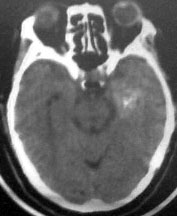

病人此次症状应与右侧丘脑及基底节出血破溃入脑室有关。

左侧颞叶考虑血管畸形,右侧丘脑及基底节出血破溃入脑室

1右丘脑脑出血破入脑室; 2左颞叶avm。如果去年有则更加证明是avm,如果去年没有则可能是钙化尚少,显示不明显. 建议强化

左侧颞叶病灶密度不均,似见点状钙化,支持血管畸形性病变.右侧病变为出血.